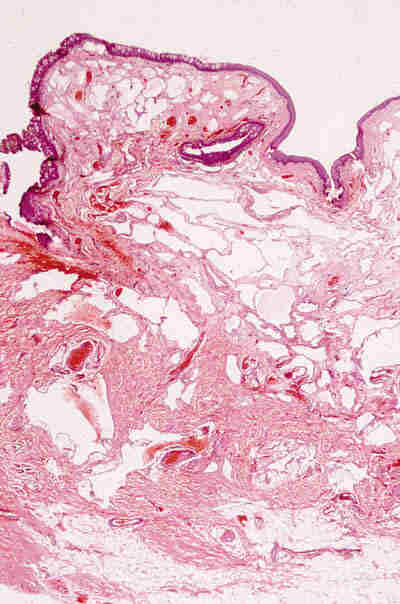

* Quistes dermoides: Se encuentran revestidos por un epitelio

estratificado queratinizante con anejos dérmicos (folículos y glándulas

sebaceas) en su pared (figura 2). La aparición ocasional de elementos

mesodérmicos (cartílago) no modifica el concepto de quiste dermoide.

Figura 2. Quiste dermoide. La pared del quiste muestra un

revestimiento por epitelio escamoso queratinizante y contiene glándulas

sebáceas y estructuras pilosas.